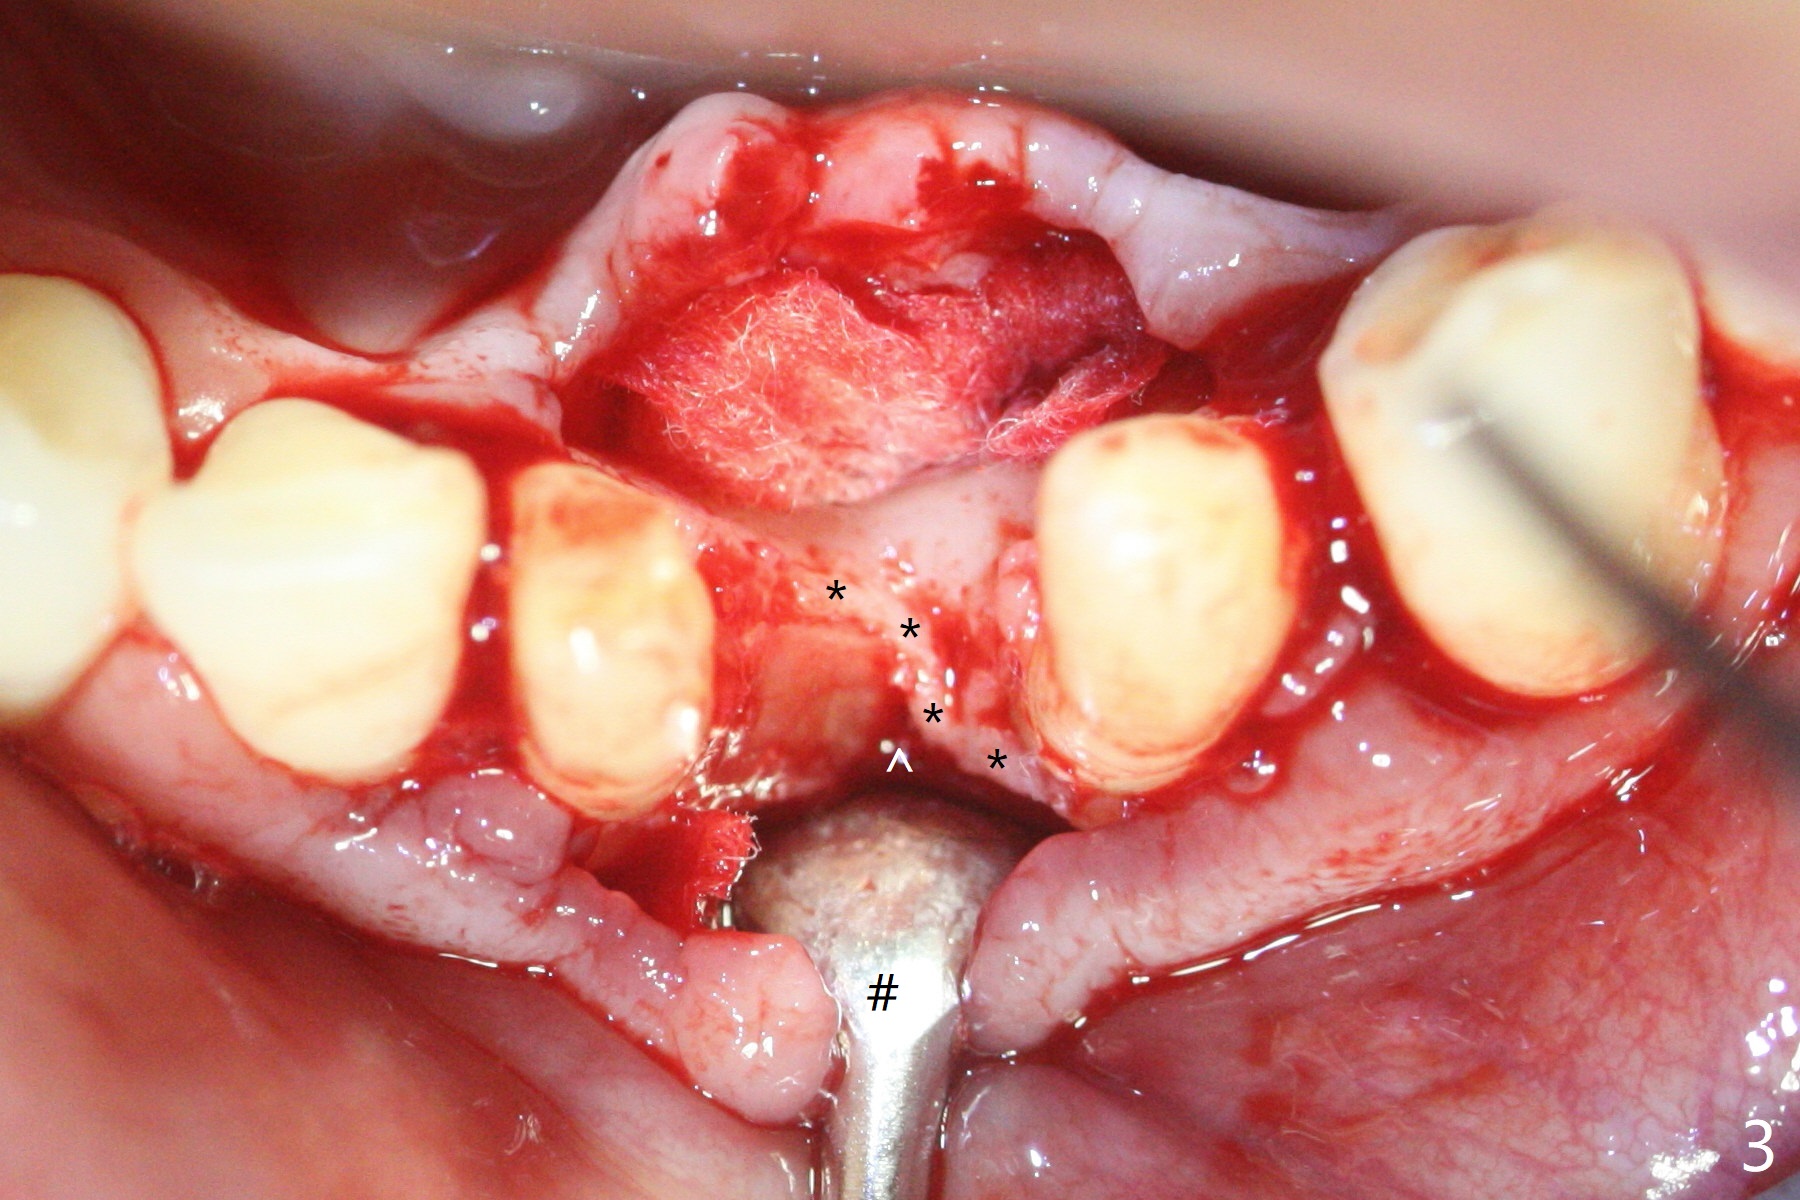

经过深洗以及改善口腔卫生,术前下前牙区牙龈基本没有红肿,但是缺牙处牙龈凹陷(图一,二:箭头),这个现象代表什么?如何影响手术进路?其实后者部分是因为牙龈与下面骨质(骨嵴)粘连(图三:*)产生的,分离粘骨膜瓣时不小心撕裂颊侧牙龈(图三(骨膜分离器下面:#),造成后来缝合困难,需要多用一个胎盘膜)。如果术前仔细分析CT 3D图像(图四,五)可以发现严重颊侧骨壁凹陷(图三:^)以及骨嵴(图四:*),事先抽血制备PRF膜和粘性骨粉,植骨效果好些(图六)。术中发现缺损,再抽血会拖延手术。最后将就用血调袢骨粉,使用胶原膜和胎盘膜覆盖(图七,八)。颊侧裂口术后十天愈合了(图九,十)。术后一个月颊侧牙龈凹陷,牙桥边缘(图十一:箭头)粗糙,临时牙桥取出,调整边缘,有利于局部卫生(图十二)。术后两个月桥边缘光滑(图十三:箭头),局部卫生和牙龈凹陷有所改善。病人将一个半月后回来取模。Return to Protect Graft 前磨牙即种 101 Xin Wei, DDS, PhD, MS 1st edition 04/30/2021, last revision 07/03/2021